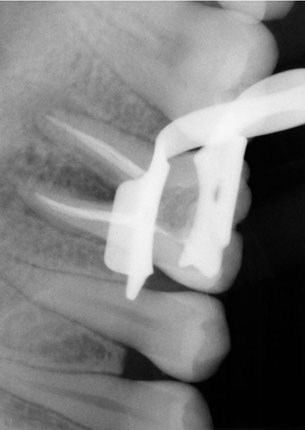

During the root canal treatment, the nerve and the pulp are eliminated and the tooth gets cleaned inside, the root is filled with the correct materials and the next step is the reconstruction of the dental crown. All this treatment is performed by applying local anesthesia, the same anesthesia that is used in a common procedure.

The root canal treatment gives you more lifetime of usage to your dental piece. At Dental Evolution Cancun we recommend avoiding the extraction of your dental piece, instead, you can choose this treatment and we promise you it’s a painless procedure; due to the cutting edge technology, rotating instrumental, ultrasound system, and to our “digital radiographs” that all performs a crucial role in the root canal process as well as our expert crew who will look after you with the professionalism that we always provide.